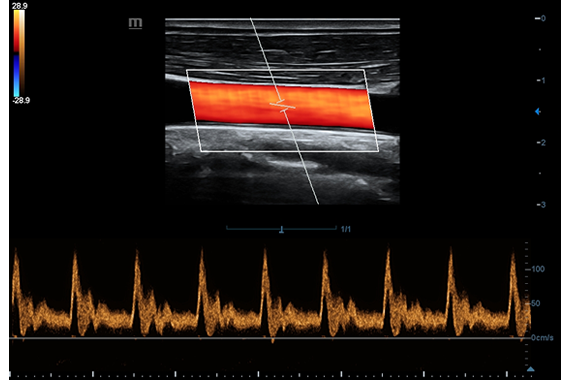

Клинические изображения

- Импульсно-волновой допплер (PW)

- Цветной допплер (Color Doppler)

- Импульсно-волновой допплер (PW)

- Цветной допплер (Color Doppler)

- Ангиология